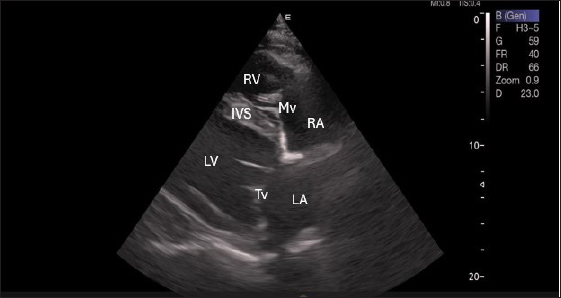

By positioning the probe perpendicularly in the fourth intercostal space or longitudinally in the fifth space with a little clockwise rotation, the interventricular septum, ventricles, and atria could be observed in the caudal long-axis four-chamber view (Fig. 1). From this vantage point, all camels could be seen to have a left ventricle, mitral valve, interventricular septum, right ventricle, and tricuspid valve. Figure 2 shows that in the short-axis image of the cardiac ventricles obtained with a little clockwise rotation at the 4th ICS, only the right ventricle, interventricular septum, and left ventricle were visible. Here, the dimensions of all camel heart were measured in M mode. The right parasternal two-dimensional short-axis pictures of the heart’s base in the first frame were used to determine the LA/Ao ratio, by applying 2D and M mode (Figs. 3 and 4). Despite some difficulties, we successfully acquired a pulmonary image by attempting to acquire the right ventricular outflow tract for the right short axis at the level of the great vessels.

Fig. 1. Right parasternal longitudinal axis (systole) of 16 years racing camel showing Lv=left ventricle, Rv=right ventricle, Ivs=Inte3r ventricular septum, Mv=mitral valve, and Tv=tricuspid valve.

Figure 5 shows an image of the ventricles, atria, and interventricular septum in the caudal long-axis four-chamber view acquired by positioning the probe perpendicularly in the fourth intercostal space or longitudinally in the fifth intercostal space with a little clockwise rotation. Every camel had a perfectly normal heart anatomy, including ventricles, tricuspid valve, mitral valve, and atria on both sides. During the fourth ICS image of the LVOT, the probe was turned slightly further cranially and twisted somewhat counterclockwise (Fig. 6). No camel is complete without an oblique aortic cross-section.

Fig. 5. Left parasternal longitudinal axis (Systole) of 16 years racing camel showing Lv=left ventricle, Rv=right ventricle, Ivs=interventricular septum, Mv=mitral valve, and Tv=tricuspid valve.